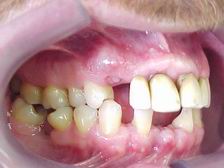

Vista Lateral Direita (ANTES)

Vista Lateral Esquerda (ANTES)